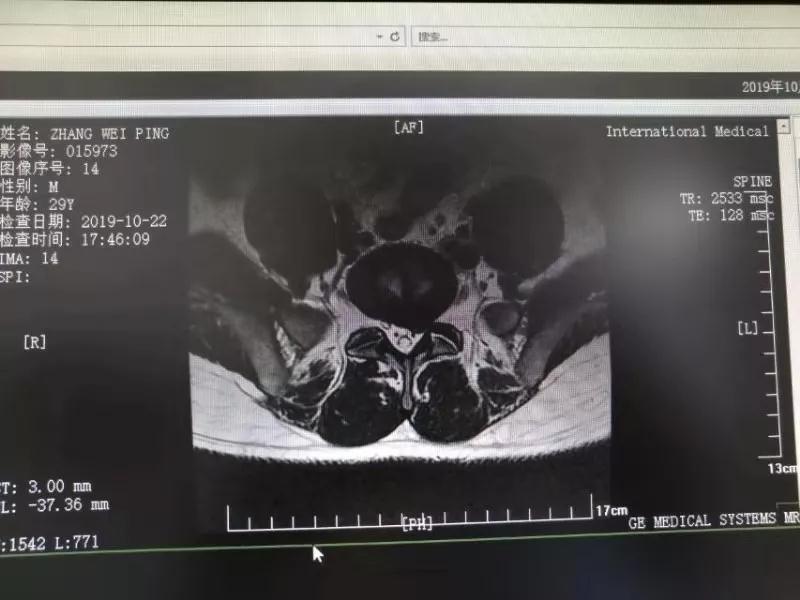

10月25日,29歲的患者小張了解到西安國際醫(yī)學(xué)中心骨科醫(yī)院專家云集,一大早便在家人的陪同下,來到西安國際醫(yī)學(xué)中心骨科醫(yī)院就診?!拔已闯掷m(xù)2年多,最近感冒后腰痛癥狀明顯加重了?!毙埫媛犊喑?,因?yàn)殚L期腰痛、左下肢放射性疼痛,她晚上睡覺不能平躺,經(jīng)常疼得睡不著,需要口服止痛藥物才能有所緩解。走路走不了多遠(yuǎn)就開始腿抽的疼,嚴(yán)重影響到工作和生活。

結(jié)合患者的檢查以及年齡情況,王自立副院長推薦讓專門研究椎間孔鏡技術(shù)王雄勛主任給小張做微創(chuàng)的椎間孔鏡手術(shù)。該手術(shù)創(chuàng)傷很小,不影響脊柱的穩(wěn)定性,尤其適合于椎間盤突出的年輕患者,懷著對骨科醫(yī)院專家的信任,小張與家人商議后,接受手術(shù)治療。